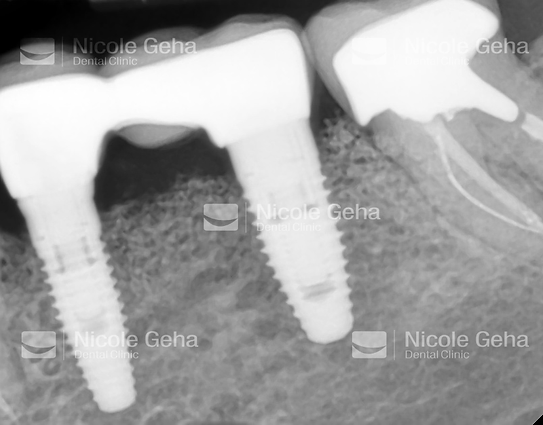

MULTIPLE IMPLANTS

case 2: before replacing the bridge

case 2: after implant placement

case 2: after